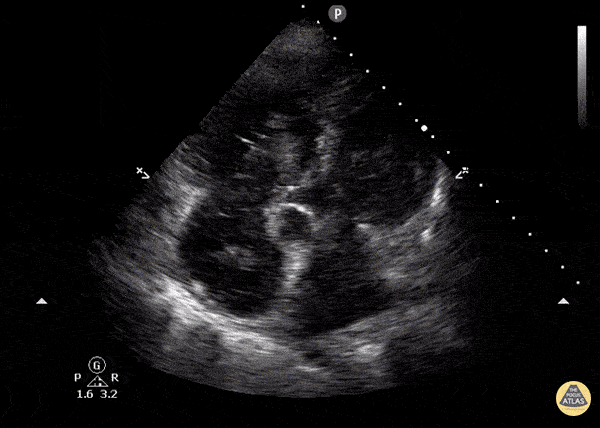

Elderly female with hypotension and shortness of breath and back pain presenting in extremis. Treated with TPA for a RA thrombus and saddle pulmonary embolism. Dr. William Scheels